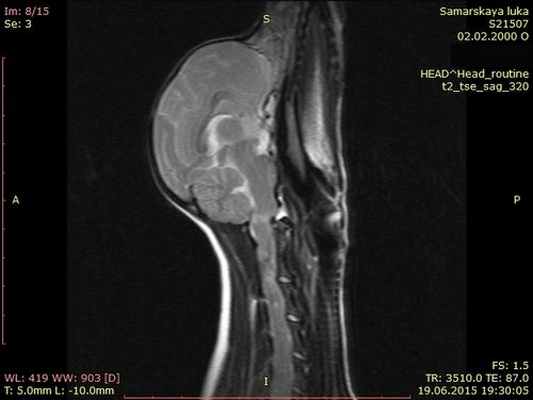

На мрт исследовании нашего пациента – здесь представлена сагитальная Т2 взвешенная последовательность, определяется смещение аксиального позвонка в дорсальном направлении по отношению к атланту, дислокация дорсальной дужки атланта к задней черепной ямке с тяжелой компрессией как мозжечка, так и спинного мозга.

Мрт пациента с краниоцервикальной мальформацией (Впадина Дьюи, сирингомиелия в шейном отделе)